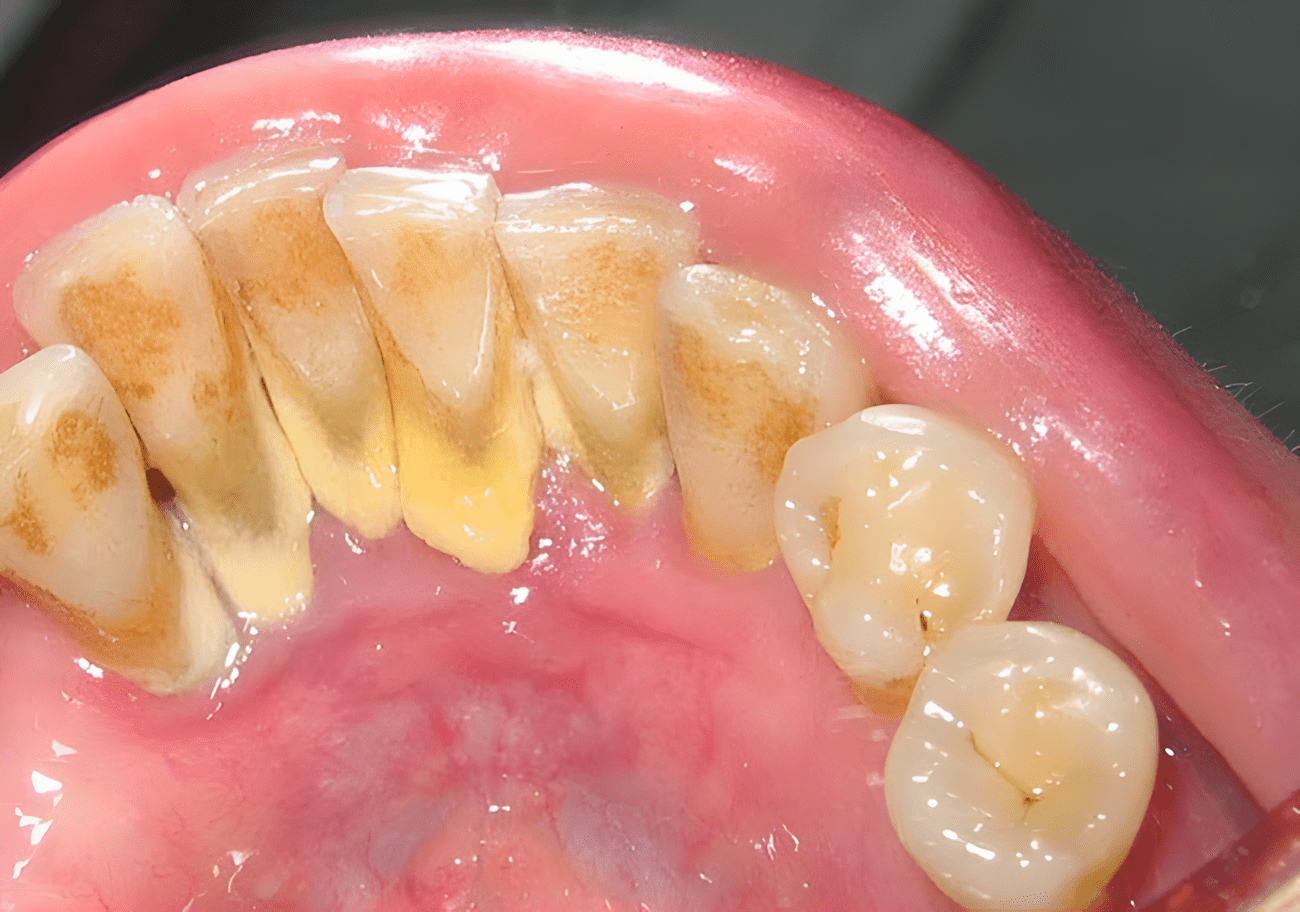

Tandplak, ook wel tandsteen genoemd, veroorzaakt vaak problemen als een slechte adem, terugtrekkend tandvlees en ontstekingen. Deze plaat bestaat feitelijk uit biofilms; dit zijn kalksteenstructuren waarin bacteriën leven. Deze biofilms zorgen ervoor dat bacteriën kunnen overleven, omdat ze hen niet alleen beschermen tegen aanvallen van het immuunsysteem, maar ook tegen antibiotica.